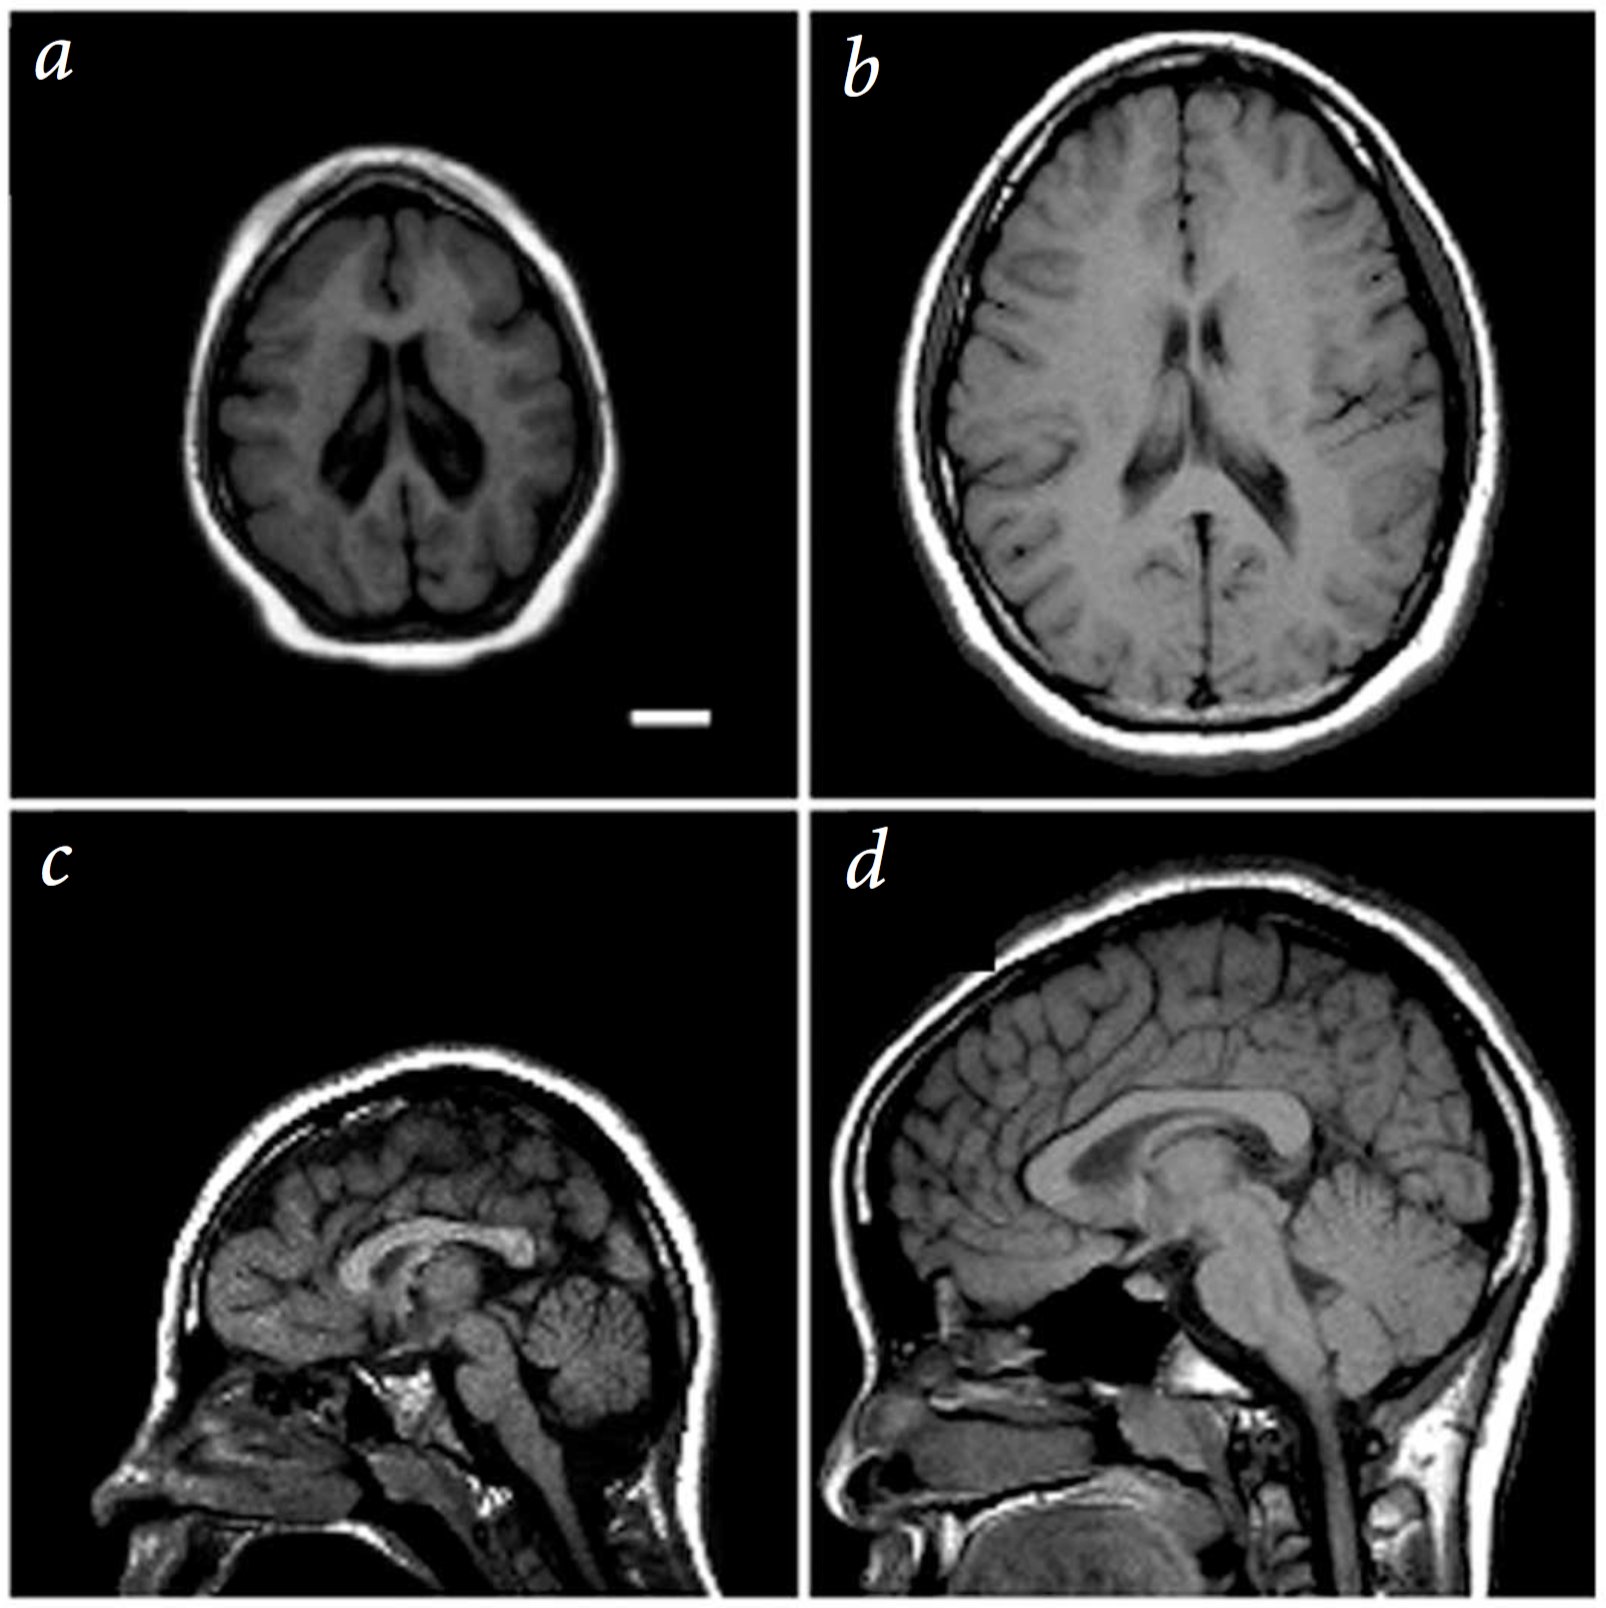

A single mutation can lead to dramatic brain size defects

Mutation in a spindle pole gene call ASPM1 (altered mitosis during brain development)

Bond:2002, see also Neuroscience 5e Fig. 1.1

Note:

Now mutations in single genes in the right place in our genome can cause drastic effects on the formation of our brain’s wiring.

For example, shown here is a person with a mutation in ASPM1 a protein used to make spindle poles for mitotic stem cells during embryonic development.

But most single gene mutations do not cause such drastic effects, with a more subtle and complex set of genetic and environmental risk factors causing neurological disease, similar to and probably exceeding the complex etiology of cancer.

2cm scale bar. left 13yr old female patient. right 11 yr old control.